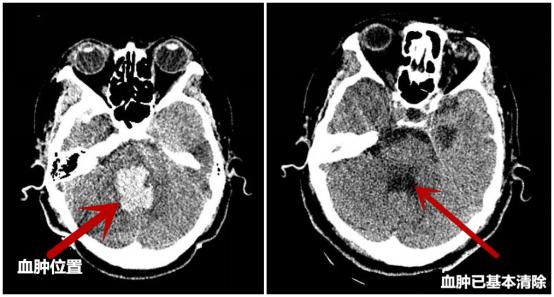

术后复查CT,与术前CT对比血肿明显减少

术后,简国庆院长说道:机器人”辅助定位立体定向脑干血肿穿刺碎吸引流术,与传统手术相比,定位更精确,创伤小;并且通过术前精准的设计穿刺路径,能避开重要神经和血管,使患者能以最小的损伤取得最佳的治疗效果,使患者脑干的大血肿转化为小血肿,同时采用冲洗、药物溶血、引流等方式排空血肿,使患者获得生存机会,后期通过康复促醒提高患者生存质量。

术后15天复查CT

与术前CT对比血肿已基本清除